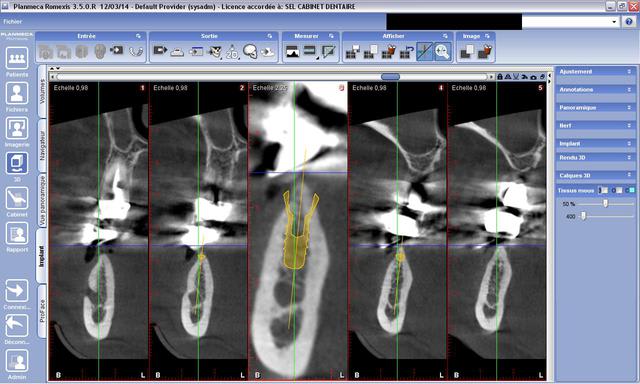

Afin d'avoir une piqûre de rappel sur une planification pour un implant mandibulaire...

Etant donnée un Os dense de la corticale d'ou par défaut une faible vascularisation de cet os, faut il mettre un implant de plus faible diametre afin d'avoir une parfaite osteointegration de l'implant avec l'os spongieux ?

photo en exemple